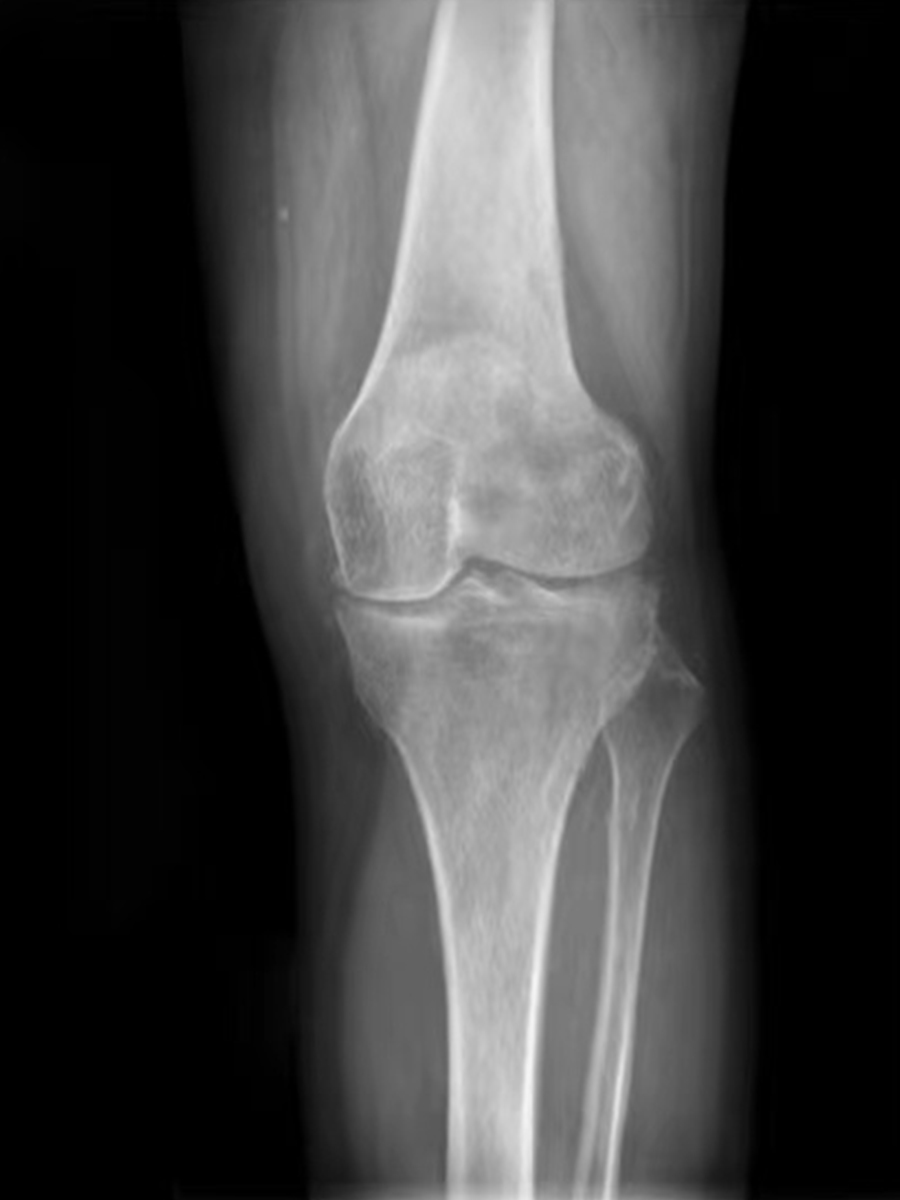

ˋ▽ˊ 年轻人膝盖疼要不要重视?滑膜炎表现及治疗方法大揭秘!接着讲讲西医治疗方法。西医一般会先让你做个检查,像核磁共振啥的,就像给膝盖做个“高清拍照”,看看里面的情况到底咋样。如果确诊是滑... 找到适合自己的治疗方法。只有这样,才能让你的膝盖早日恢复健康,重新活力满满地去拥抱生活。可别让小小的滑膜炎,影响了你的快乐生活啊...